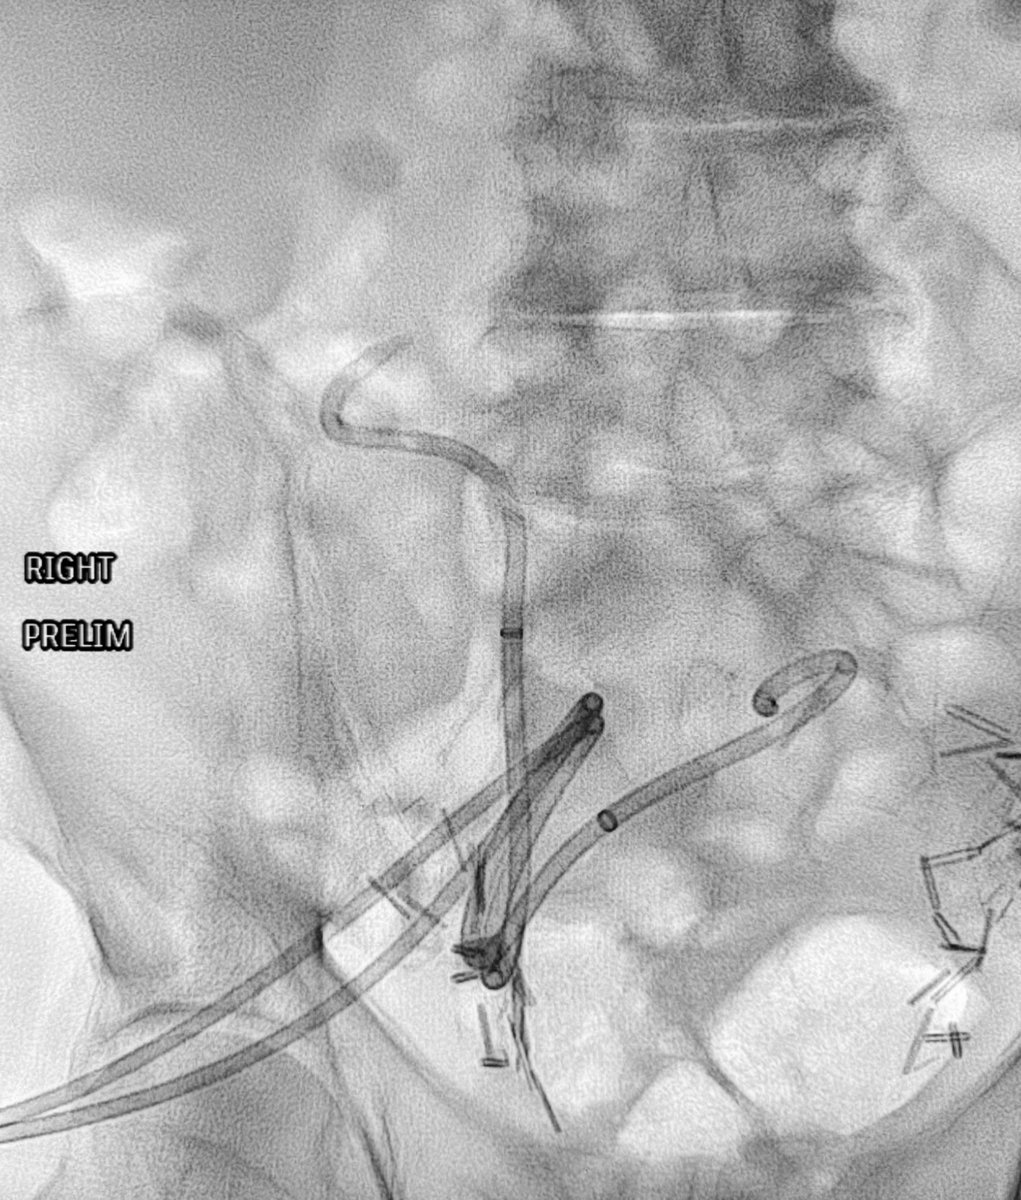

#CTO of Nephroureteral stents! Can’t cross with any wire on shelf! What’s your rec to help out your junior colleague to swap them ? May be your trick can come handy & help @SIRRFS one day ! @kmadass I know it ain’t arterial 😁 @keithppereira @SDhandMD @IRKhalsa @IR_Doctor